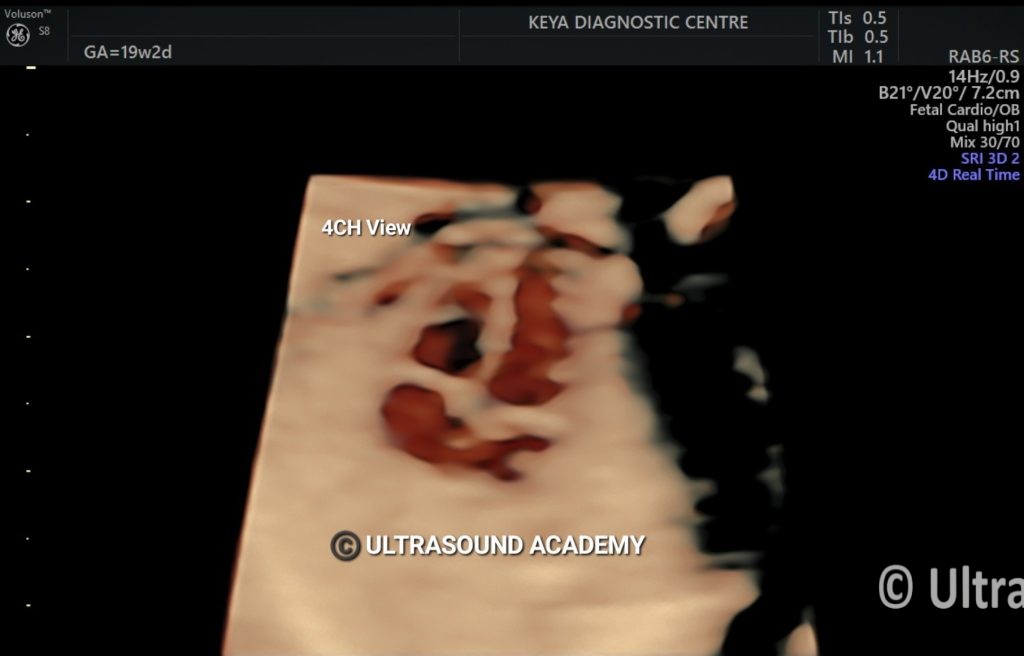

NORMAL 4D FETAL HEART

4D evaluation of fetal heart is shown using 4D STIC surface rendering.

Showing 4 chamber view of fetal heart with inter-atrial and inter-ventricular septum. Bilateral AV valves are also seen.